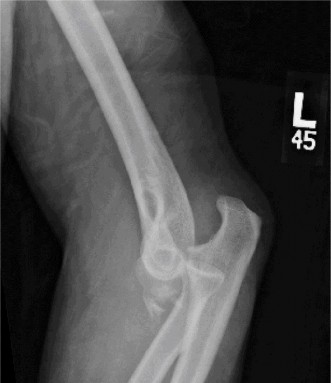

A 54-year-old male presented to the ED with left elbow pain after sustaining an injury in a low speed motor v…